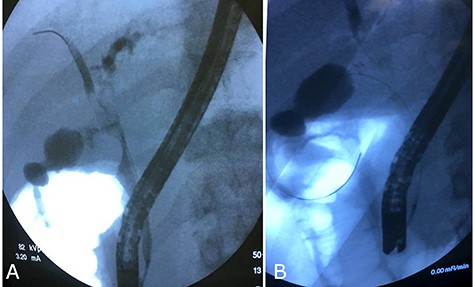

After 40 days, patient had no signs of liver and biliary complications and kehr’s tube appeared normally placed. Blood count and bilirubin was normal with alkaline phosphatase 447 U/l, AST 112 U/l, ALT 162 U/l. Trans-kehr cholangiography showed normal size of CBD (Fig. 3), so it was removed and replaced with a single plastic biliary stent (9-cm length and 10-Fr diameter) through an ERCP.